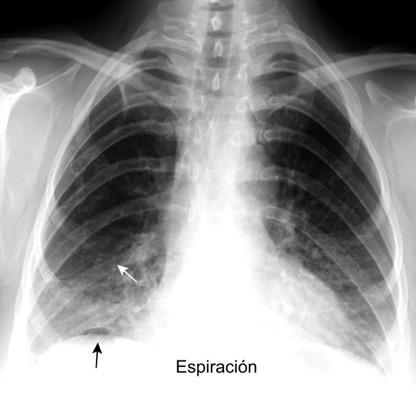

91. NEUMOTÓRAX EN ESPIRACIÓN

Visualización de la pleura visceral separada de la parietal por aire Borde externo Convexo Localización: Ápex pulmonar

El aire penetra en inspiración en el espacio pleural. No sale en espiración. Desplazamiento importante de mediastino y silueta cardiovascular.

M. Bradley et al. Value of routine expiratory chest films in the diagnosis of pneumothorax.Arch Emerg Med.1991, F. Schramel, et al. Expiratory chest radiographs do not improve visibility of small apical pneumothoraces by enhanced contrast.Eur Respir J. 1996,